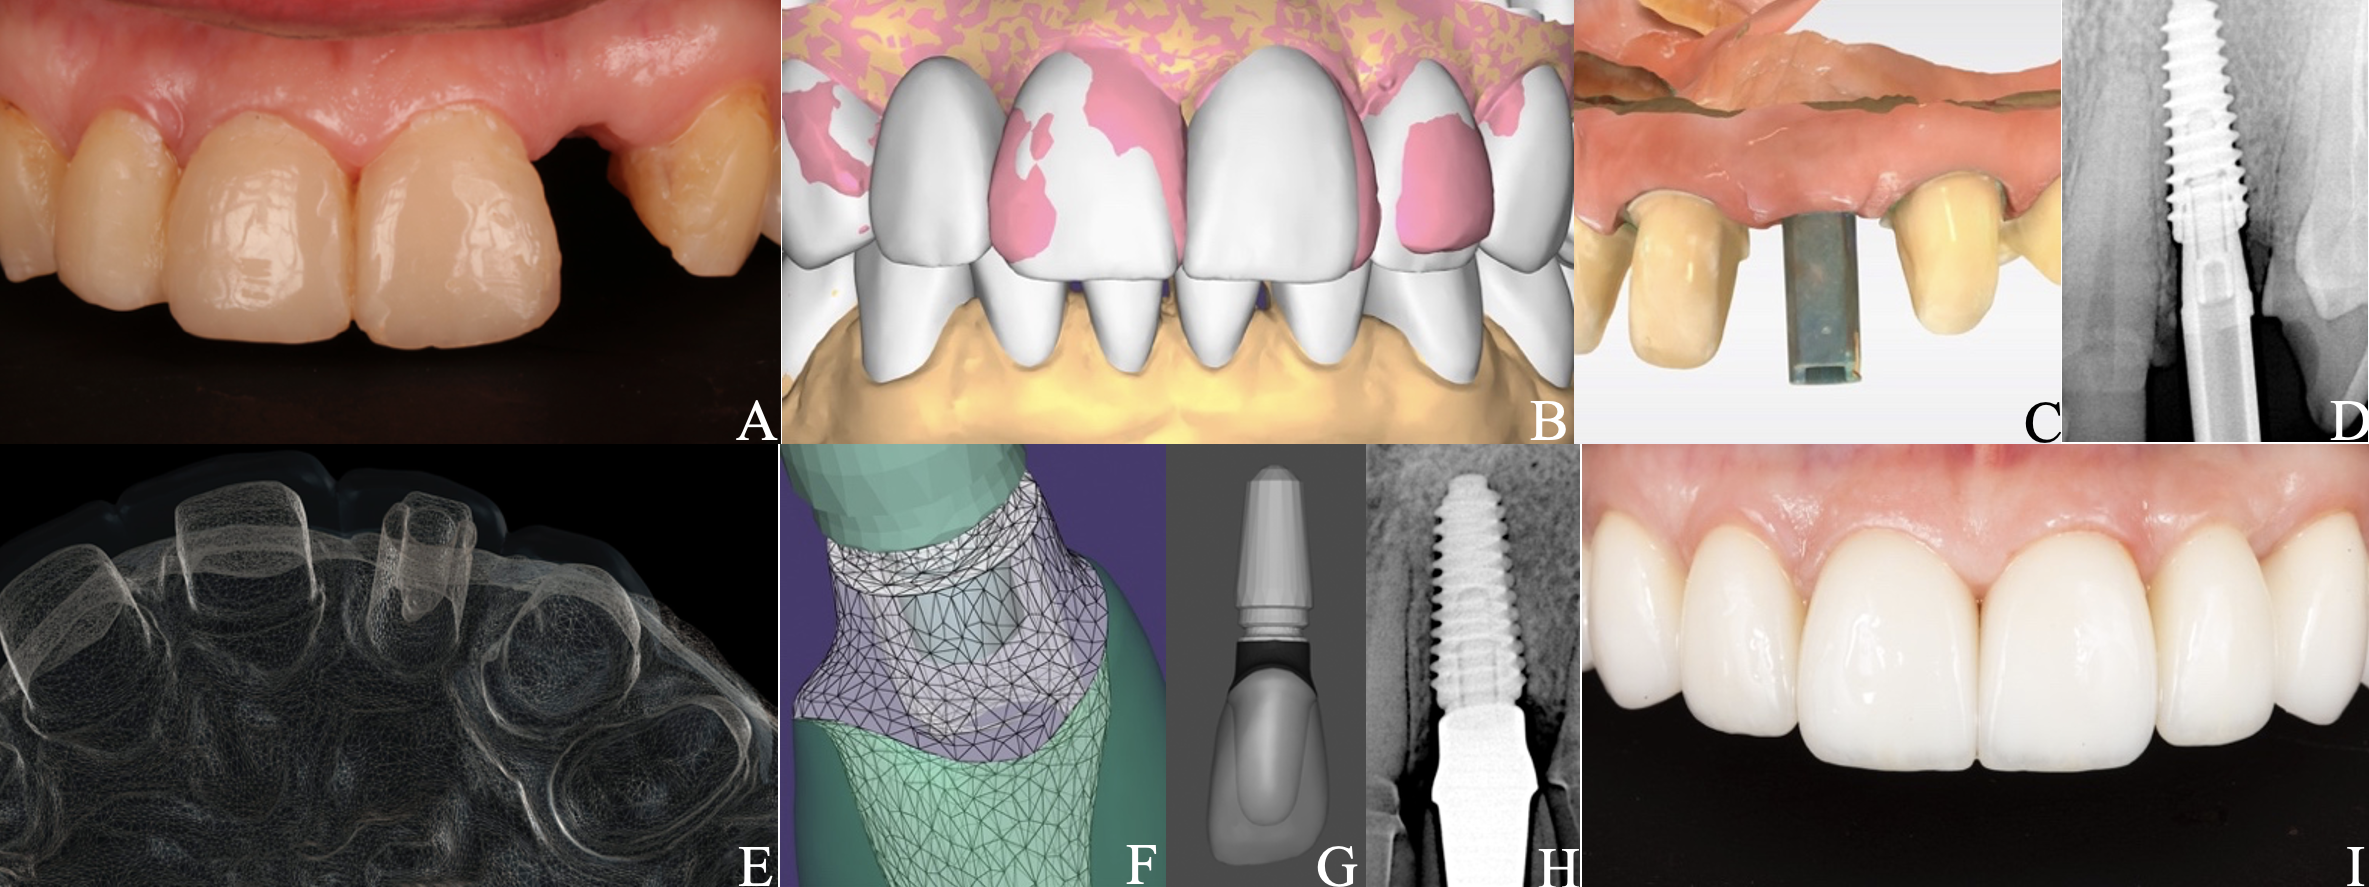

A 50-year-old woman with a fracture of the tooth 2.2 (Pan A) was referred to our clinic. After cone-beam computed tomography, atraumatic root extraction with preservation of the vestibular bone wall was performed. A sequential drilling protocol using the AnyRidge® system (MegaGen) along the palatal wall of the socket was applied for an implant size of 4.0×11.5 mm. Upon the implantation navigation was not used. Additionally, bone grafting of the socket was performed with a xenograft (BMG-20, BIO-GEN®; BIOTECK). The next step was to use a free gingival graft (FGG) harvested from right maxillary tuberosity (RMT) for the “poncho” technique. At the time of implant opening, a preliminary scan (CEREC® Primescan AC; Dentsply Sirona) for a digital wax-up of the tooth anatomy (Pan B, DentalCAD 3.1 Rijeka [exocad]) considering the patient's aesthetic preferences was performed. Implant opening was done using the roll technique and installing an individual modified healing abutment (composite [Gradia® Direct AO3; GC] on a titanium platform, made clinically). The repeated gingival plasty, FGG from the RMT, was also performed. Panels C and D show control scan of the maxillary teeth with scan marker on the implant and digital radiography (Genoray X-PORT-IV-e; Genoray Co) four weeks before permanent prosthetics. Panel E illustrates evaluation and verification of the project in Smilecloud (Smilecloud SRL). A platform marker from a Zero Bone Loss Concepts Kit® (MegaGen) was used to select the appropriate height of the permanent platform (ZrGEN 4015, Ø4.0, AnyOne®; MegaGen) on the individual zirconia abutment (Pan F, DentalCAD and exocad webview 1.6.18). On top of which an InitialTM LiSi Press (GC) lithium disilicate crown (Pan G, DentalCAD) was cemented in the laboratory after fitting for optimal aesthetics. Screw fixation of the restoration to the implant was done at 35 Ncm torque. An adhesive protocol was applied for lithium disilicate ceramic restorations on the teeth. Panel H highlights control radiography at month six. Intraoral condition after 6 months (Pan I) showed nice pink-white aesthetics. Panels A and I were obtained using Canon EOS 6D full-frame digital camera (Canon) with Canon Macro Twin Lite MT-26-EX-RT.